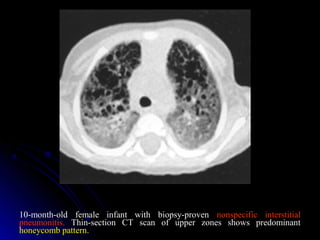

10-month-old female infant with biopsy-proven nonspecific interstitial

pneumonitis. Thin-section CT scan of upper zones shows predominant

honeycomb pattern.